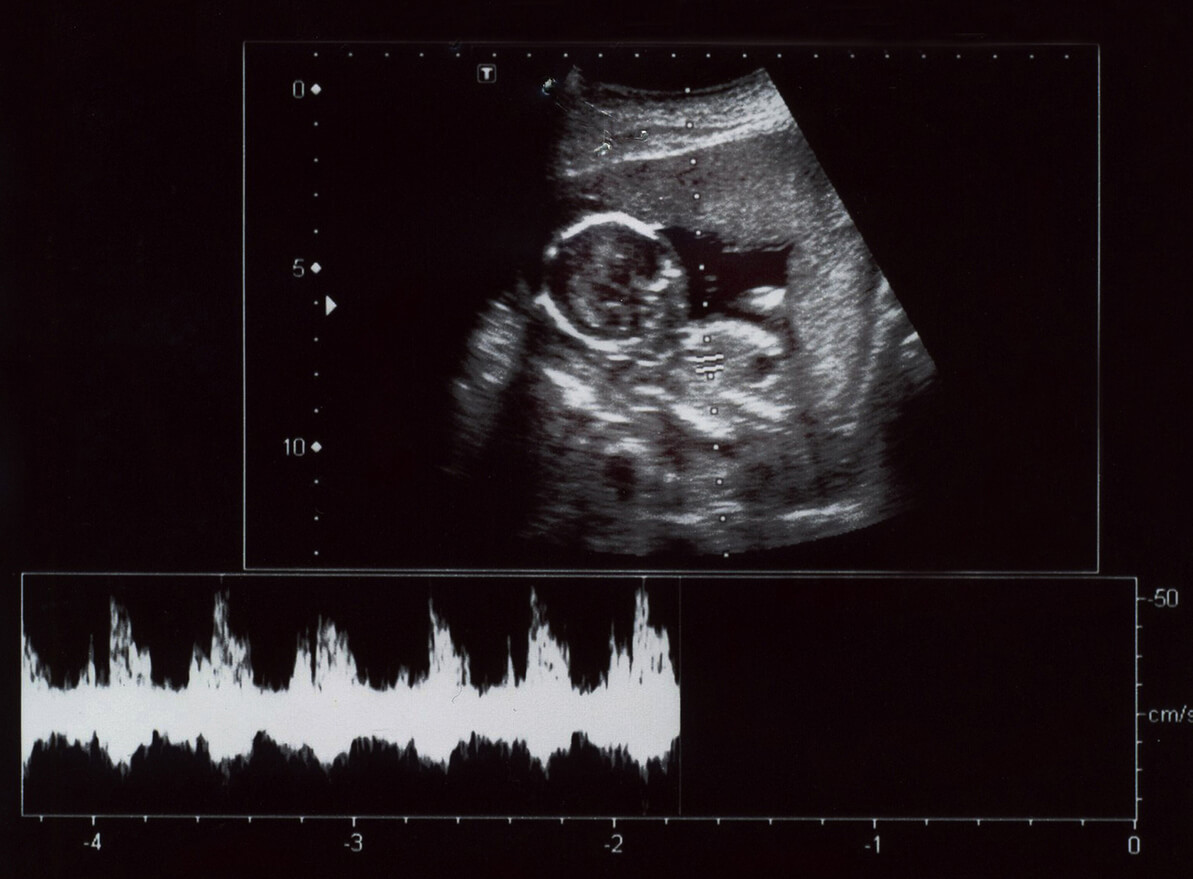

L’échographie est une méthode d’imagerie diagnostique, dans laquelle des ondes sonores à haute fréquence sont utilisées pour observer les tissus internes. Dans le cas de la femme enceinte, il s’agit d’observer le bébé qui grandit.

Les images obtenues permettent au spécialiste de voir l’anatomie du bébé et son développement tout au long des 9 mois. Ainsi que d’autres structures telles que le placenta et le liquide amniotique. De cette façon, les complications possibles peuvent être diagnostiquées en temps opportun.

- Échographie Doppler : le Doppler couleur est généralement utilisé pour l’étude circulatoire dans les veines et les artères, car on observe les fluides en mouvement. D’autre part, le Doppler pulsé étudie les vaisseaux sanguins et le cœur.

- Échographie 3D et 4D : grâce à elles, il y a une meilleure visualisation fœtale et la forme et le volume du bébé sont clairement évalués. De son côté, l’échographie 4D permet d’observer les mouvements de l’enfant en temps réel.